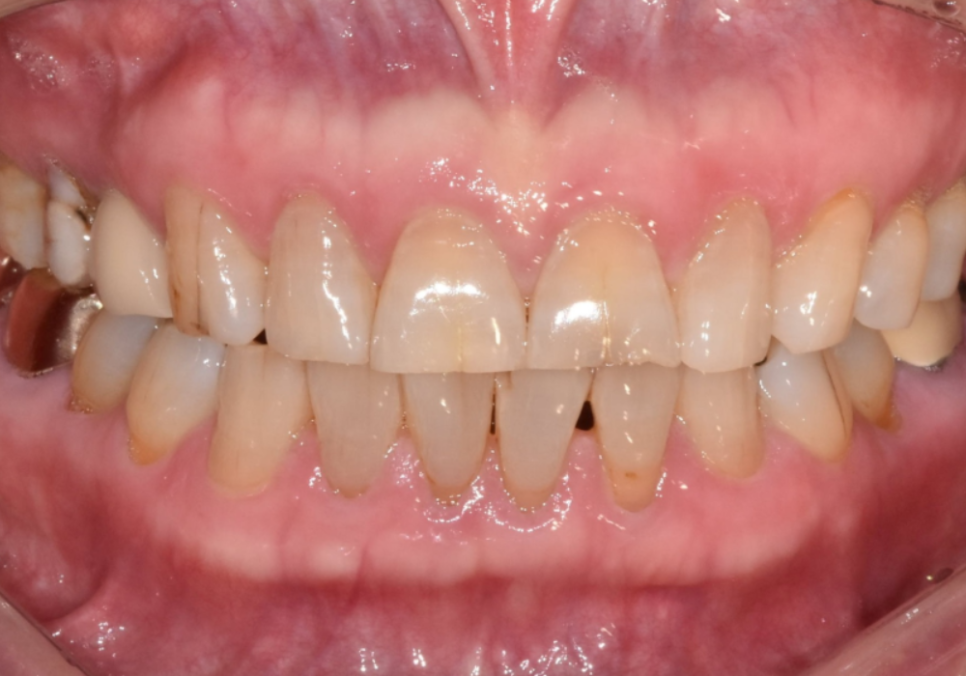

강도와 심미성을 모두 잡은

PFZ (Porcelain Fused to Zirconia)크라운을

진행하기로 했습니다.

일반 지르코니아는 강한 조명 아래서

치아가 탁하고 인위적으로 보일 수 있어요.

반면 PFZ는 안쪽은 튼튼한 지르코니아를,

바깥쪽은 심미적으로 투명한 도자기층을

층층이 쌓아 만들기 때문에

빛이 은은하게 투과되어 훨씬 자연스럽죠.

다행히 환자분은

치아 배열이 가지런한 편이셨어요.

굳이 치아들을 하나로 묶지 않아도

개별적으로 충분히 예쁘게 만들 수 있는 상태였죠.

그래서 번거롭더라도 6개의 치아를 하나씩

정성껏 따로 제작해 드렸습니다.

240201(전) 240221(후)